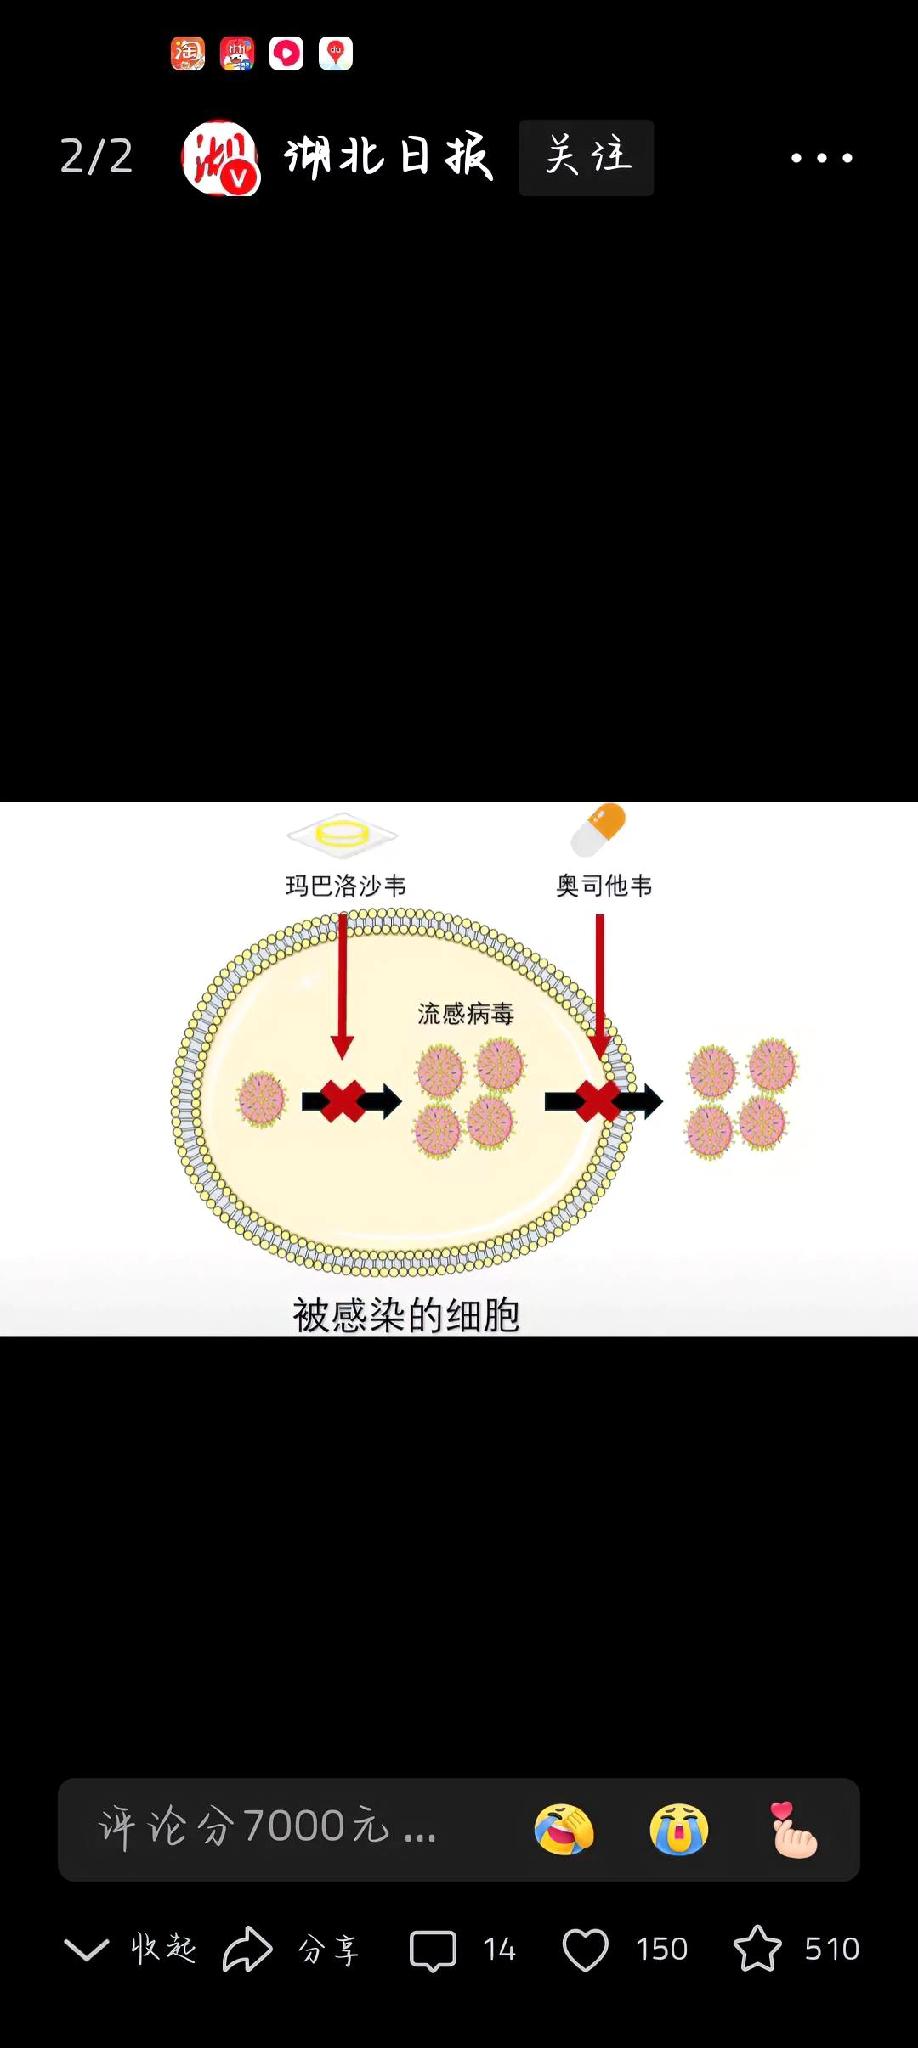

为什么病毒感染后,人还感觉疲惫无力?

因为病毒入侵后,人体就会激活免疫系统,这种激活在转阴康复后,仍旧有一段持续。

免疫系统的动员,并不是转阴后就消停了,它也有一个缓慢停下来的过程。

这种持续性的免疫激活,就会让人感觉很疲劳,好比免疫细胞一直不停的劳动,人就会感到很累。